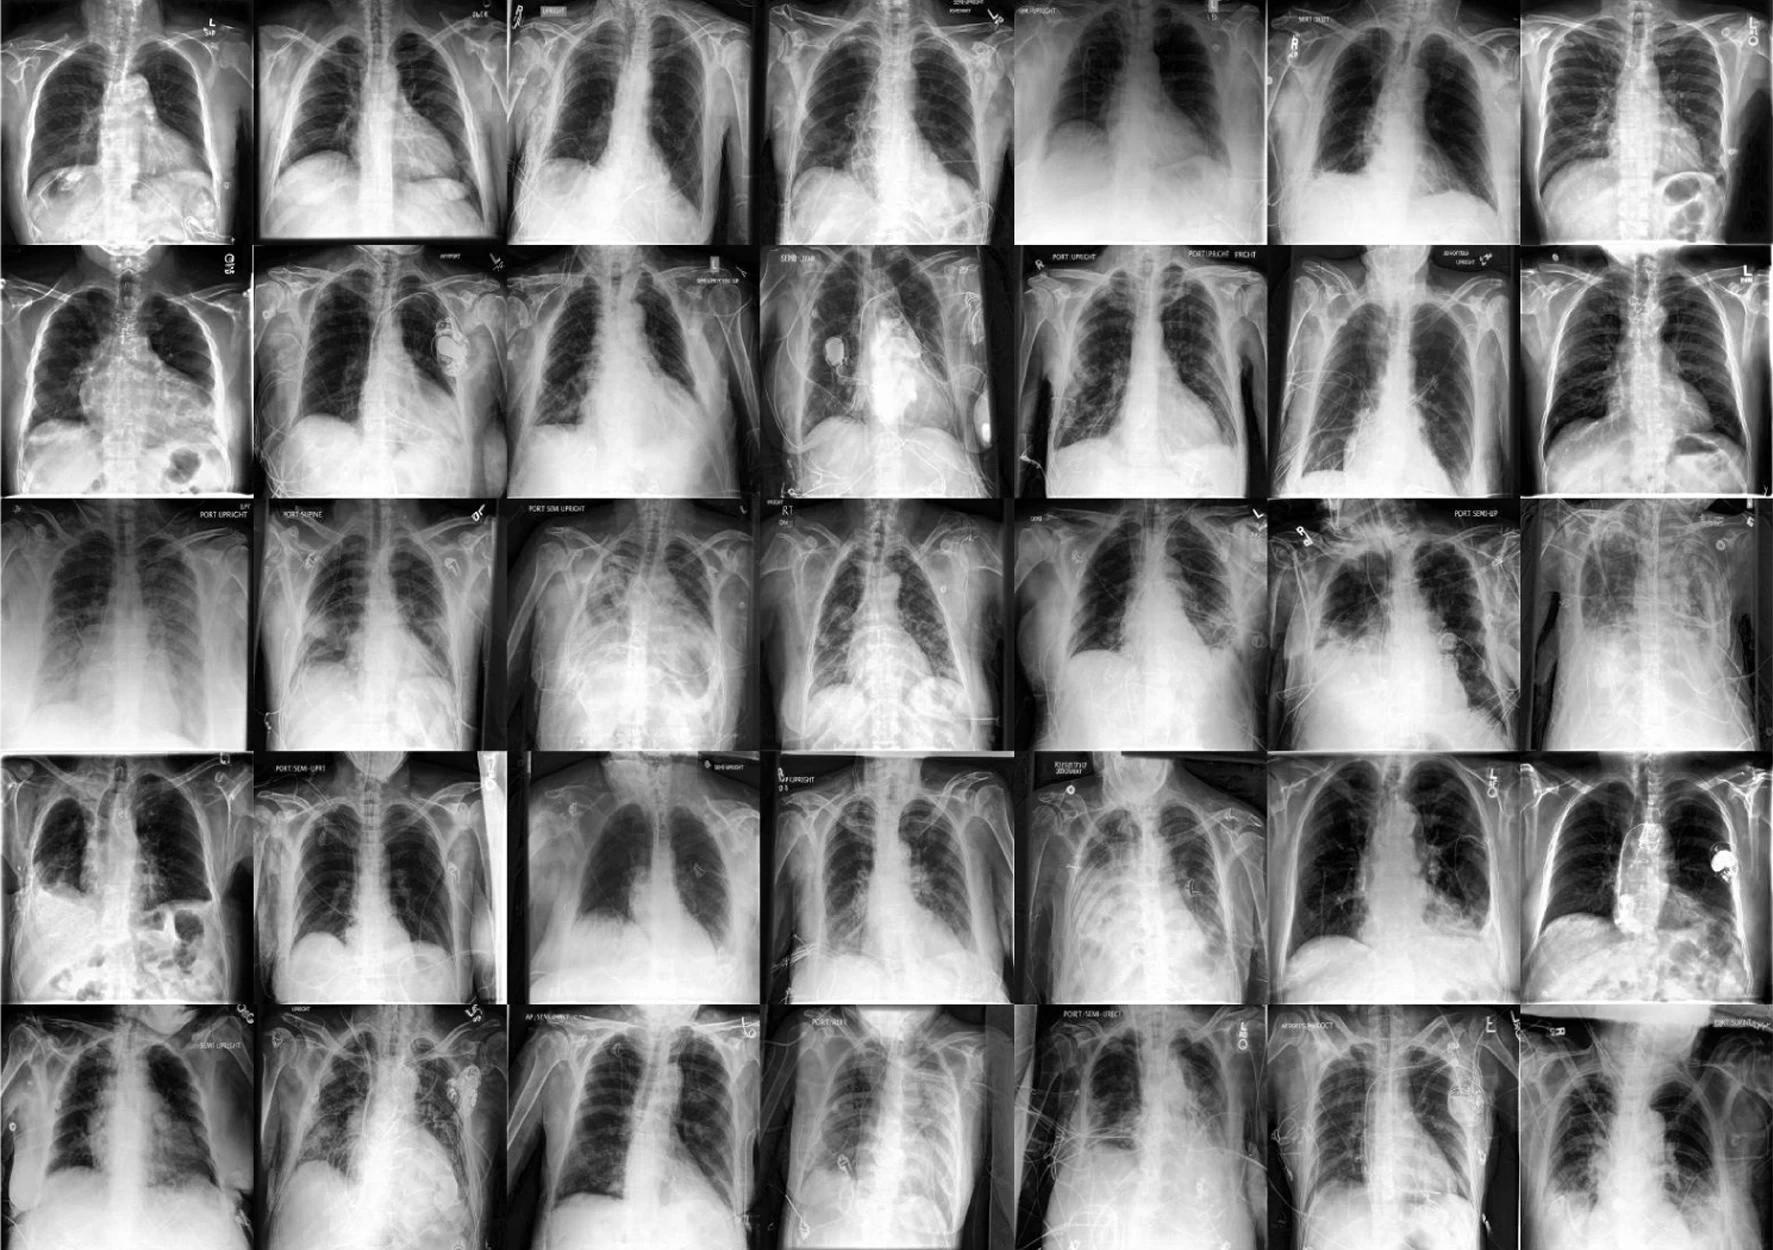

In the present study, researchers employed diffusion models to examine medical imaging situations such as histology, chest X-rays, and dermatological pictures. They used these photos to enhance the reliability and fairness of medical machine-learning models. They also utilized unlabeled data to track data dispersion and supplement actual samples. The project sought to expand the training dataset in a steerable and programmable manner.

Researchers used two big public radiology datasets, CheXpert and ChestX-ray, to create generative and diagnostic models for chest X-rays. After training on 201,055 chest X-ray instances, dermatologists evaluated the model's ability to capture primary characteristics on 488 synthetic pictures from regular and high-risk classes. They assessed the picture quality to offer a diagnosis for up to three of the approximately 20,000 common illnesses.